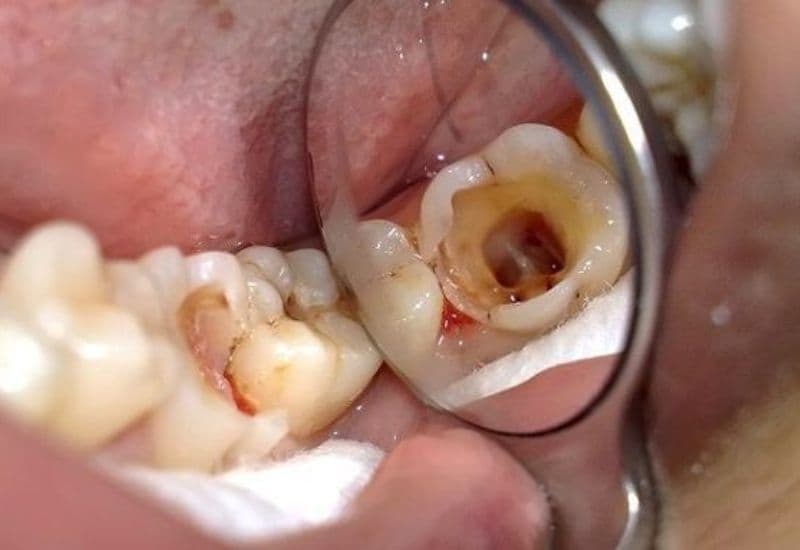

Khi sâu răng hàm trẻ em tiến triển nghiêm trọng hơn, các triệu chứng thường trở nên rõ rệt, bao gồm cảm giác đau khi nhai hoặc khi tiếp xúc với thức ăn nóng, lạnh, ngọt; xuất hiện hố sâu dễ nhận thấy trên bề mặt răng hàm; nướu quanh răng bị sâu sưng đỏ; và hơi thở có mùi hôi đặc trưng phát ra từ khu vực răng tổn thương.

3.3. Giai đoạn biến chứng sâu răng hàm ở trẻ

Điều trị tủy răng được áp dụng khi sâu răng hàm trẻ em đã lan đến tủy, nhằm loại bỏ phần tủy bị nhiễm trùng, làm sạch ống tủy, sau đó hàn kín và phục hồi thân răng. Trong trường hợp răng không còn khả năng cứu chữa, bác sĩ sẽ chỉ định nhổ răng, đồng thời đặt khí cụ giữ chỗ để đảm bảo răng vĩnh viễn mọc đúng vị trí.